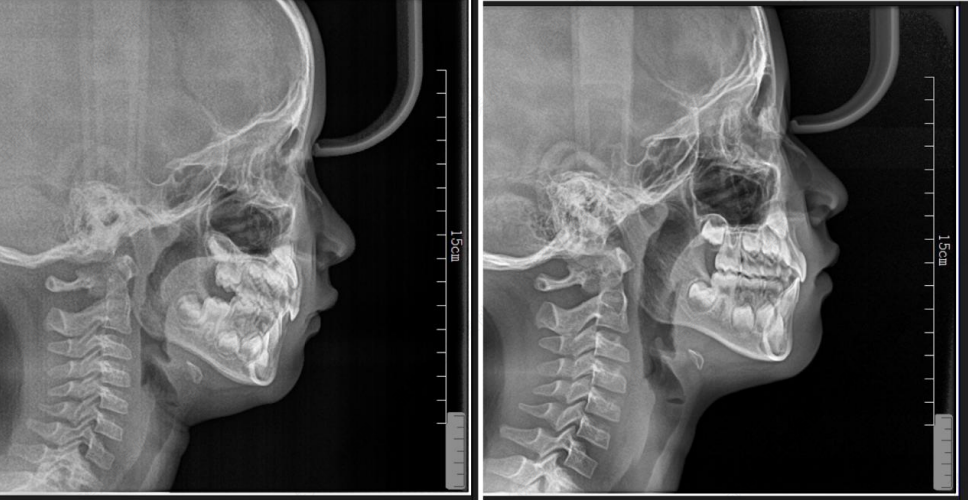

矫正行动:比如高角骨性下巴后缩,我们更多的希望是逆时针旋转,因此牙齿矫正过程中,我们要做好对上前牙的转矩控制,同时上牙不能过长,下前牙必须要足够的压低,并且是直立于基骨,这样可以下巴不会后退。

如果想要引导下巴往前伸,还需要控制好后部的颌平面角度,颌平面一定是平的,不能是倾斜的,如果颌平面越斜,会让下巴后缩。通过这三点来改变下颌骨的位置,从而可以改善下巴后缩的问题。

矫正效果:成人不必焦虑年龄限制,明确主诉功能or美观,选择好正畸医生,制定合适的正畸方案。把咬合的一些因素去掉,把下巴行的情况,尽量引导出来,所以看起来下颌骨位置好了,有下巴了。

所以正畸医生做的就是这三点:上前牙的位置的控制,下前牙位置充分直立,还有颌平面的角度调整,通过这三点来改变下颌骨的位置,从而可以改善下巴后缩的问题。